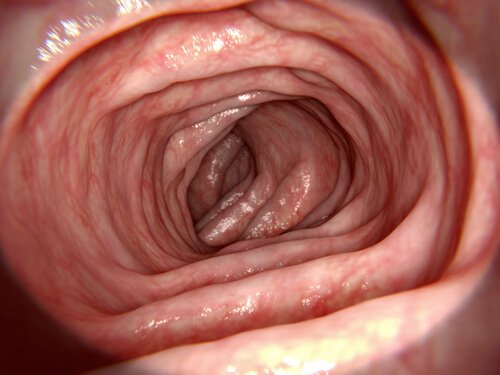

배설물이 직장에 도달하면 벽을 팽창하여 근층간 신경총을 통해 구심성 신호를 보낸다. 신호에 대한 응답으로 결장에서 나오는 연동파가 직장을 향해 아래쪽으로 흐른다. 이렇게 되면 항문에서 대변을 밀어낸다.

근층간 신경총은 내항문 괄약근을 이완하는 억제 신호를 방출한다. 그 결과 연동파가 항문에 도달하면 배설물이 계속해서 앞으로 움직인다.